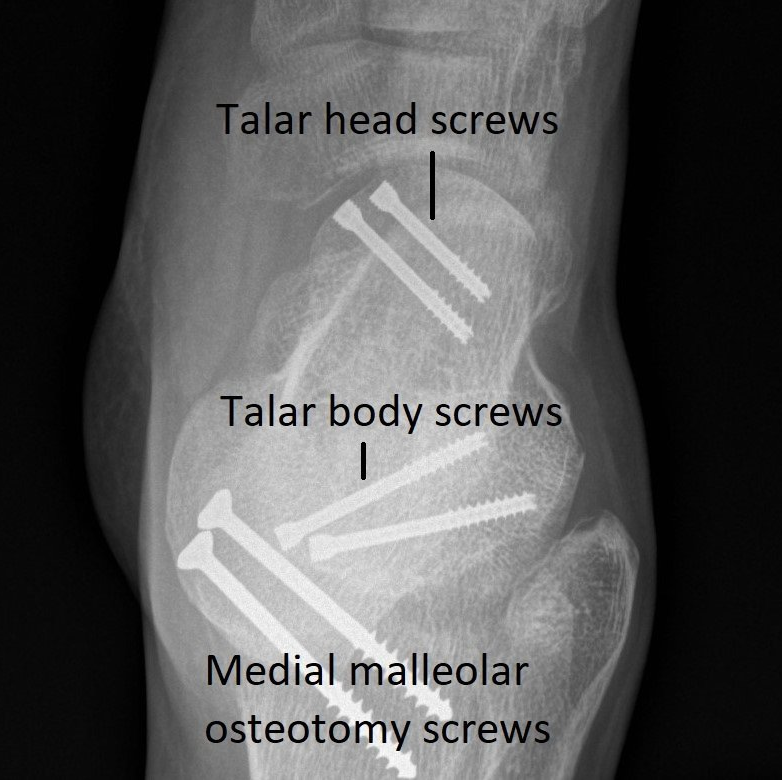

- X-rays (see image)

These imaging investigations show which part of the talus is broken and how badly. This determines both the need for surgery and the risk of long-term complications. These injuries can lead to severe ankle and hindfoot osteo-arthritis.

Talar fractures can involve the head, neck, body or processes of the talus.

- Surgical Treatment: If the fractured bones have shifted out of position, surgery to realign and stabilize the talus with metal screws and/or plates is required. After surgery, people need to use crutches and wear a "moon-boot" for 8 - 12 weeks. Physiotherapy is required to restore movement.